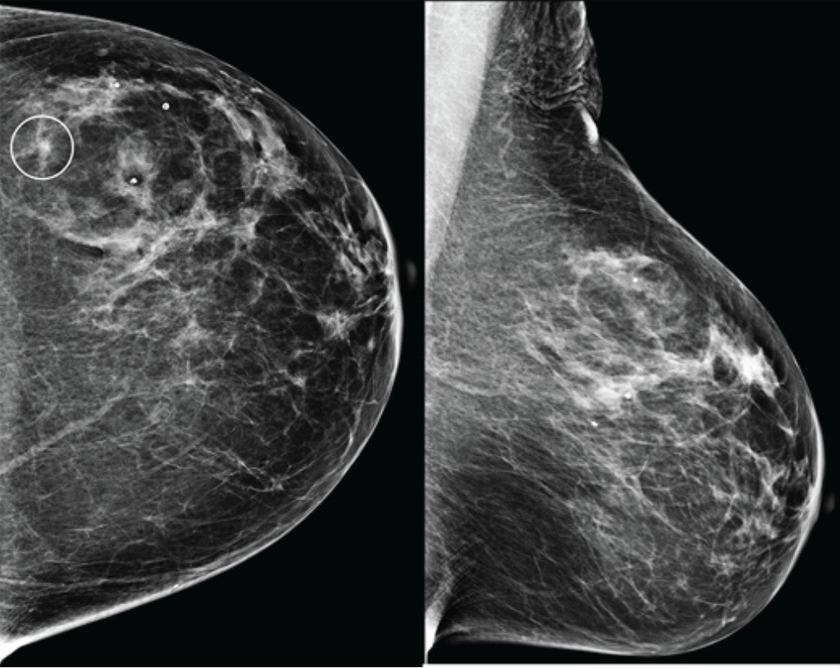

В конце августа 2025 года американский стартап Calidar представил инновационную систему 4D-маммографии, которая выводит точность диагностики злокачественных образований молочной железы на новый уровень. Эта платформа визуализации использует рентгеновскую дифракцию и искусственный интеллект для проведения исследования на молекулярном уровне.

Первая в своем роде система 4D-маммографии, разработанная компанией Calidar, позволяет решить существующие проблемы. Устройство измеряет, как рентгеновские лучи рассеиваются на молекулярном уровне: данный процесс известен как рентгеновская дифракция. Это создает уникальную структурную сигнатуру, которая отражает внутренний состав ткани молочной железы.Гид по российским системам PAM (Privileged Access Management)

В отличие от традиционных рентгеновских снимков, которые основаны на форме и плотности, рентгеновская дифракция предоставляет дополнительную диагностическую информацию о том, из чего состоит ткань. Эти специфичные данные позволяют классифицировать раковые и доброкачественные образования с точностью, в четыре раза превышающей показатели традиционных систем визуализации.[1]